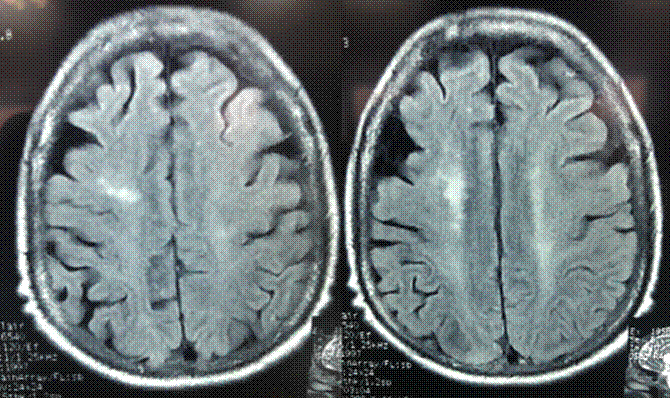

Durante la hospitalización se decidió también suministrarle a la paciente doxasosina a dosis de 4 mg/día, con lo cual, de forma paulatina, recobró el nivel de consciencia sin reaparición de crisis epilépticas y con cifras tensionales de 150/80. De esta forma, fue dada de alta y se ordenó seguimiento por consulta externa a los 30 días con resonancia de control (Figura 2), donde se observó desaparición de las lesiones corticales (posibles causas de las crisis epilépticas) y disminución de estas en sustancia blanca subcortical, las cuales pudieron estar relacionadas con leucoaraiosis periventricular. Para ese entonces la paciente se encontraba asintomática.